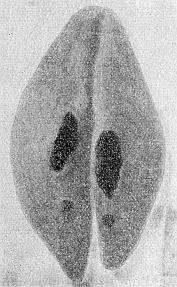

Da haben wir eine ganze Menge darüber erfahren, wie die Organe im Alter verändert werden. Aber all das können wir erst verstehen, wenn wir das Mikroskop zu Hilfe nehmen, die Organe alter Leute mikroskopisch untersuchen. Sehen wir uns z. B. ein Stückchen Niere von einem Menschen an, der aus Altersschwäche gestorben ist (Abb. 17). Da sind an einer Stelle noch gut erhaltene Nierenzellen zu sehen, die ein Nierenkanälchen bilden, wie es sich für eine normale Niere nicht besser gehörte. Aber wir finden auch Nierenkanälchen, die ganz zusammengefallen sind, wo sogar die Lichtung der Kanälchen geschwunden ist. Die Zellen dieser Kanälchen sind verkleinert, „atrophisch“, wie man sagt. Diese Zellen haben einen Altersschwund erfahren. Genau so ist es mit den Zellen der Leber, der Drüsen, des Gehirnes und der Organe sonst. Weil die Zellen der Organe klein, atrophisch geworden sind, sind eben bei dem alten Menschen die Organe kleiner als in jüngeren Jahren. Es findet also im Alter eine Atrophie der Zellen statt, ein Schwund der lebendigen Zellsubstanz. Der Schwund der lebendigen Substanz der Zellen kennzeichnet alle Organe des gealterten Körpers.

Abb. 17. Horizontalschnitte durch Nierenkanälchen aus der Niere eines alten Menschen. a mit noch gut erhaltenen Zellen; man sieht hier deutlich die Lichtung des Nierenkanälchens. b und c mit atrophischen Zellen: die Kanälchen sind zusammengefallen, eine Lichtung ist nicht mehr vorhanden. Stark vergrößert. Nach Ziegler. Etwas schematisiert.